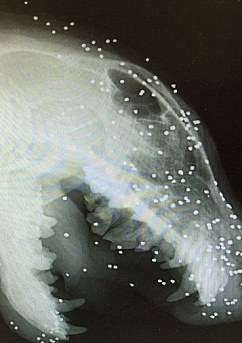

▼那天Liz发现Eric的嘴部有囊肿,所以带牠去医院检查,照了X光才发现,牠的头脸内埋着50多颗铅弹,有些甚至深入了骨头。除此之外,牠身上还有被其他狗嘶咬的旧伤。

▼Eric出现囊肿就跟牠的旧伤有关。牠有半颗犬牙镶在肉里,明显遭受过虐待。兽医根据牠的伤情推测,牠被领养前应该是一只「斗狗」。牠的眼睛全盲,也跟被铅弹射击有关。

▼遭受过这样重的伤害,Eric却没有因为败血症死去,反而坚持了下来,这简直就是个奇蹟。兽医表示,牠头脸肿的子弹太深,就算手术也无法全部移除。手术难度很大,费用也很高,治疗后牠也要带着一些子弹活下去。Liz知道Eric的伤势后非常难过,现在她正在努力筹款,希望Eric能够接受更好的治疗,以后的生活也更舒适。